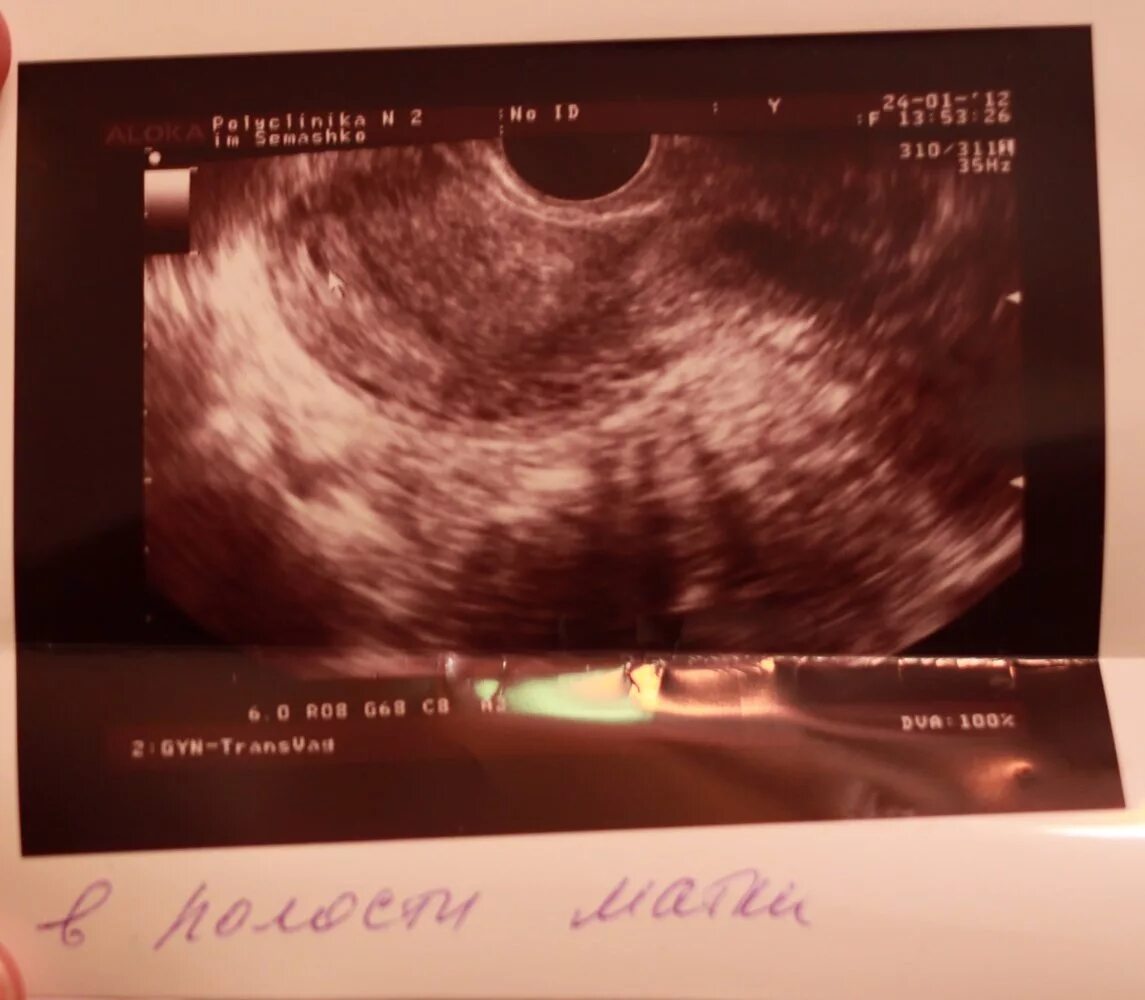

Плодное яйцо видно при хгч